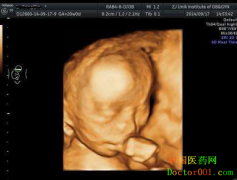

据 青岛新阳光妇产医院 专家介绍:我国新生儿出生缺陷发生率一直居高不下,为降低缺陷儿出生率,对此,专家建议:每个孕妇在孕24-28周时进行四维彩超筛查! 什么是美国GE四维彩超? 美国GE四维彩超,超越普通四维彩超的局限性,安全无辐射显像更清晰立体,筛查畸形更准...